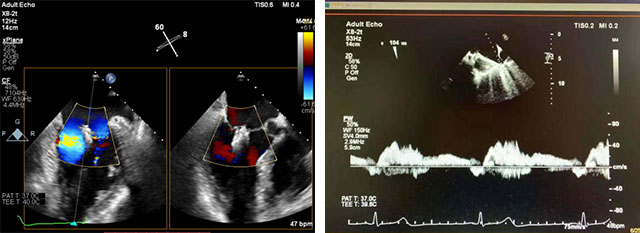

术中,在超声指导下,麻醉,体外循环团队保驾护航,瓣膜夹平稳释放,成功置入一枚drogenfly瓣膜夹,随即进行DSA及心脏超声复查,观察到植入的瓣膜夹位置精确,患者二尖瓣反流从4+减少到1+以下,手术取得了圆满成功。